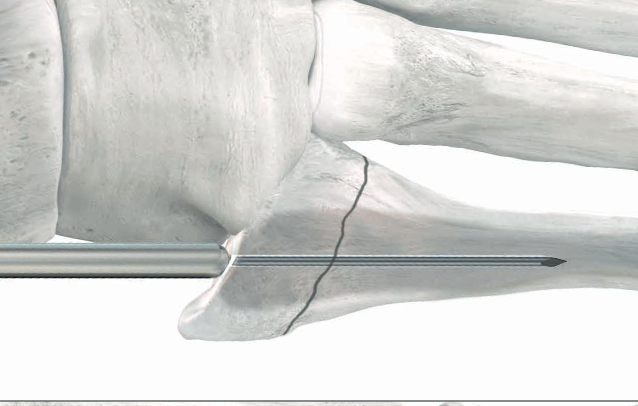

Technique

Entry point

- 5th metatarsal is not straight

- high and medial to get straight shot

- avoids plantar insertion peroneus brevis

- screw diameter 3.5 / 4.5 / 5.5 / 6.5

- screw threads must be distal to fracture site to allow compression